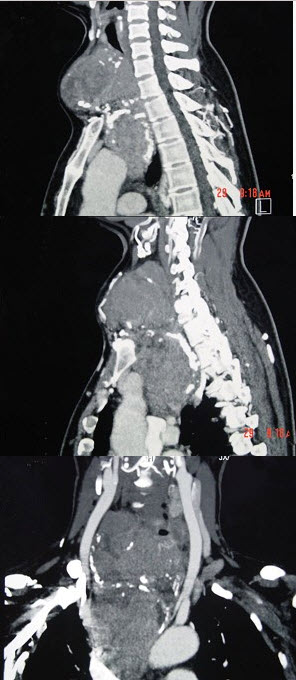

- 多项选择题女性,48岁,颈部包块3年,近来胸闷、憋气、胸痛,CT扫描如图,请选择正确的描述和答案()。

A、考虑为胸骨后甲状腺肿

D、胸骨后甲状腺肿是指甲状腺50%位于胸骨后

- A,D